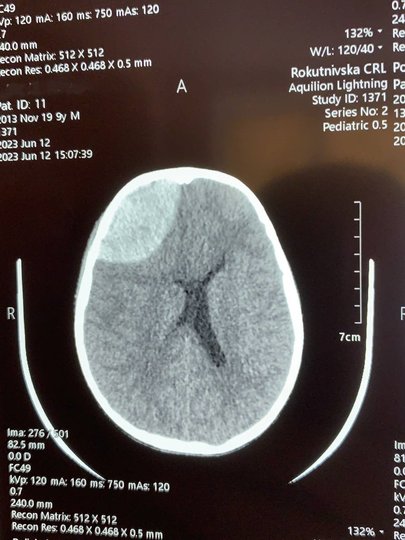

У Рівненській обласній дитячій лікарні прооперували 9-річного хлопчика, який отримав важку черепно-мозкову травму після ігор з однолітками. Хлопчик потрапив у лікарню після того, як його вдарили каменем по голові. Про успішно виконану операцію стало відомо у понеділок, 10 липня, після повідомлення прес-служби медзакладу.

У коментарі ZAXID.NET лікар-нейрохірург дитячий Сергій Романчук, який виконував операцію, розповів, що хлопчик потрапив у лікарню в важкому стані. Зокрема, він перебував без свідомості, але й були епізоди, коли пацієнт прокидався і перебував в стані психомоторного збудження: поводився неадекватно і не реагував на обстановку навколо.

За оцінками лікаря, операцію потрібно було проводити негайно, оскільки через гематому ділянка мозку, на яку тиснув кров'яний згусток, могла почати відмирати. Оперативне втручання розпочали близько 23:00, тривало воно впродовж 3,5 годин.

«Особливість цієї операції в тому, що це була велика гематома. Ми йому зняли невеликий фрагмент кістки, забрали гематому, і після цього кістку поставили назад і прифіксували спеціальними кістковими швами. Завдяки цьому в нього все швидко заросте і не буде косметичного дефекту», – зазначає Сергій Романчук.